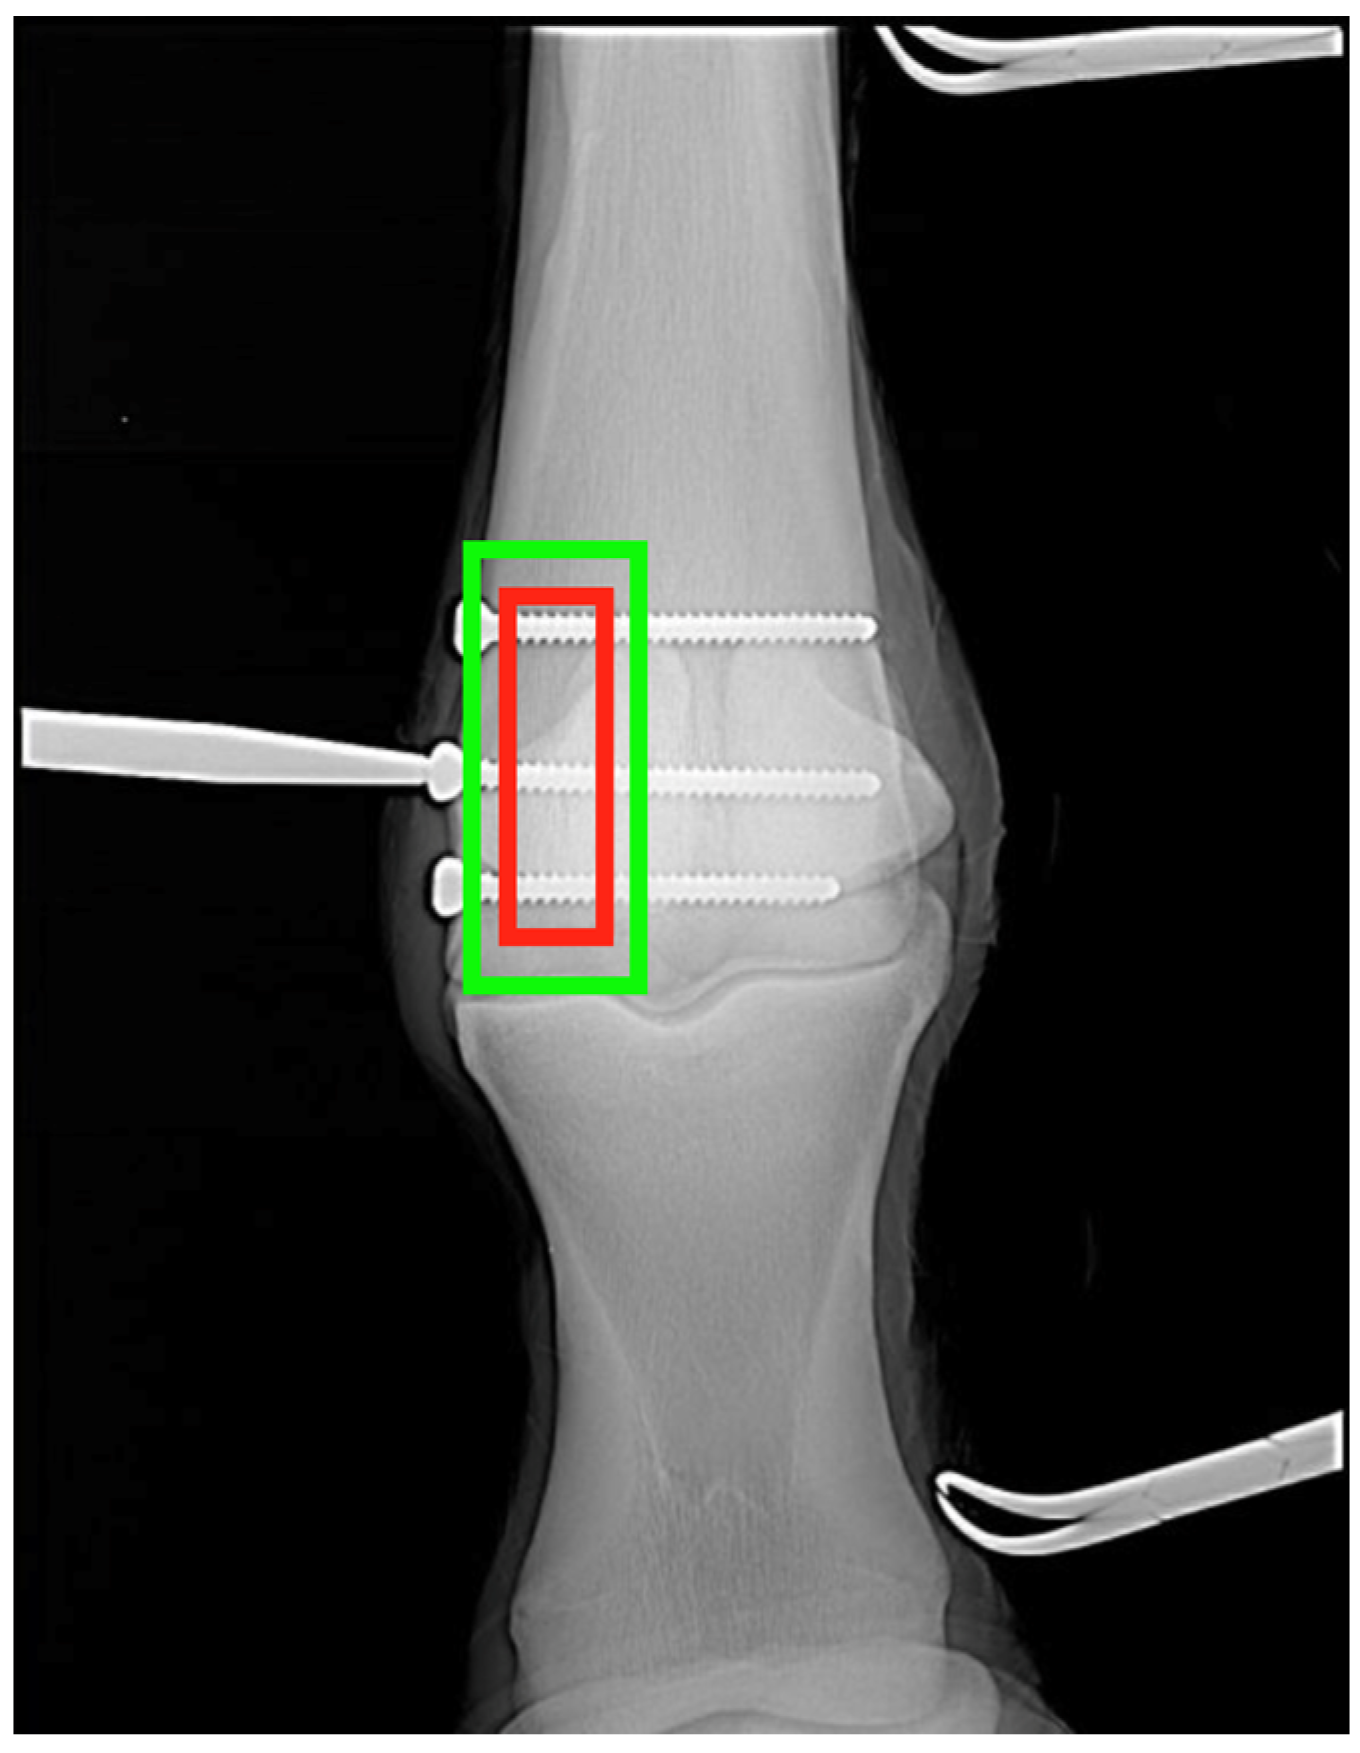

To further support the quantitative findings, exemplary visualizations of fracture localization on human and feline radiographs are shown in Figure 4. The predicted bounding boxes (green) closely align with expert annotated ground truth regions (red), demonstrating consistent spatial accuracy across species. In human images, the model reliably detects cortical disruptions and joint misalignments, while in feline images, it successfully identifies subtle fractures in small, morphologically variable bones. The results underscore the model’s ability to detect fractures across species and anatomical contexts, confirming the effectiveness of the transfer learning approach. The diverse pretraining and fine-tuning strategy enabled robust performance on both large-bone (e.g., equine fetlock, human wrist) and small-bone (e.g., feline digit) regions or thin bones (e.g., ulna or fibula).

Figure 4. Cross-species validation of fracture detection. Examples from independent test set illustrate model’s generalisability. (a) Human radiograph (MURA dataset) with accurate localization (IoU = 0.81). (b) Feline radiograph demonstrating reliable localization in small-scale anatomy (ulna of fibula) (IoU = 0.71). Ground truth = red; predicted = green.